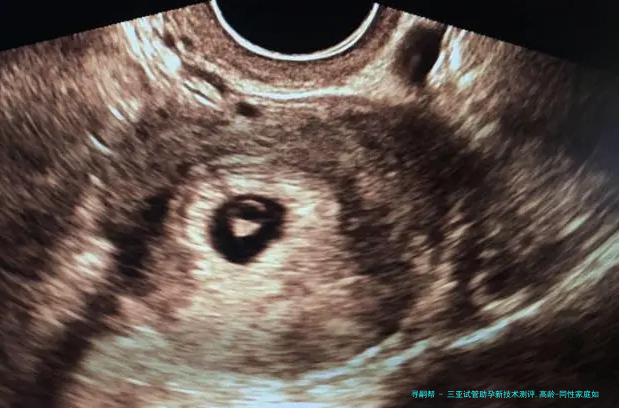

胚胎植入前基因学检查(PGD/PGS)已成为三亚主要潮流机构的标配,新一代测序技术将染色体异样检出率提升至99%以上,大幅减少高龄夫妻因卵子老化导致的早产风险。更前端的试探集结在CRISPR基因编辑,可修复地中海贫血、脊髓性肌肉萎缩症等单基因突变,虽暂处临床研究阶段,但为遗传性疾病家庭提供了新可能。

三十八岁以上女性卵子非整倍体率超60%,需首先选择备有PGT-A(非整倍体筛查) 技术的机构,结合AI预测模型筛查染色体正常胚胎,将四十二岁临床妊娠率从12%提至39%。反复移植失败者,可以借助无创胚胎基因诊断(niPGT) 通过培育液游离DNA筛查,防止活检伤害胚胎,活产率提升至75%。